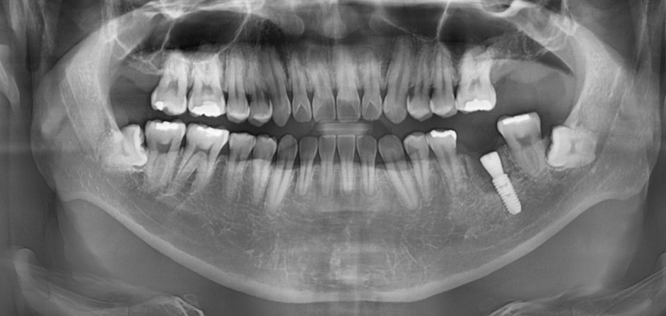

240125

임플란트 수술 후 사진입니다.

왼쪽 위 어금니

왼쪽 아래 치아 모두 발치 후 임플란트가 필요했지만

왼쪽 위 문제가 있는 치아를 발치만 진행

아래부터 수술하고

위에를 진행하기로 하였습니다.

왼쪽 아래 수술 시

치아 염증으로 이미 뼈가 많이 녹아

웅덩이처럼 파여 있었는데요.

내비게이션 임플란트 장비를 사용하여

뼈가 많은 부위에 식립할 수 있었습니다.

240208

수술 후 한 달 뒤

뼈와 잘 붙어서 바로 머리를 올렸습니다.